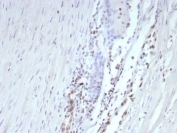

IHC staining of FFPE human prostate carcinoma tissue with ERG antibody (clone ERG/2107). HIER: boil tissue sections in pH 9 10mM Tris with 1mM EDTA for 20 min and allow to cool before testing.